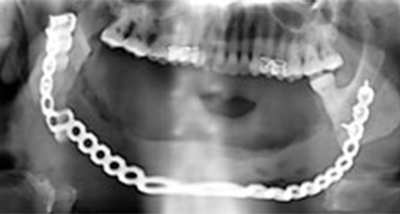

In case of extensive resection reconstruction of the defect is mandatory to the patient to restore both functions and esthetics.

The use of reconstruction plates to shape and form the defected jaw and to restore the proper contour of the face, also bone grafting is used to compensate for the osseous defect created by the resected part of the jaw. Also dental rehabilitation by means of obturators is very important to restore the quality of life for these patients.